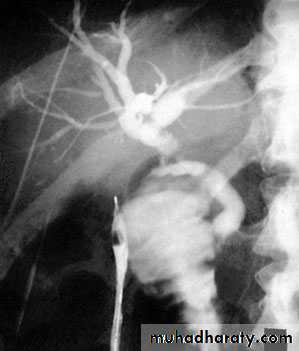

53Transhepatic cholangiogram showing a stricture of thecommon hepatic duct

Al-Madena copy